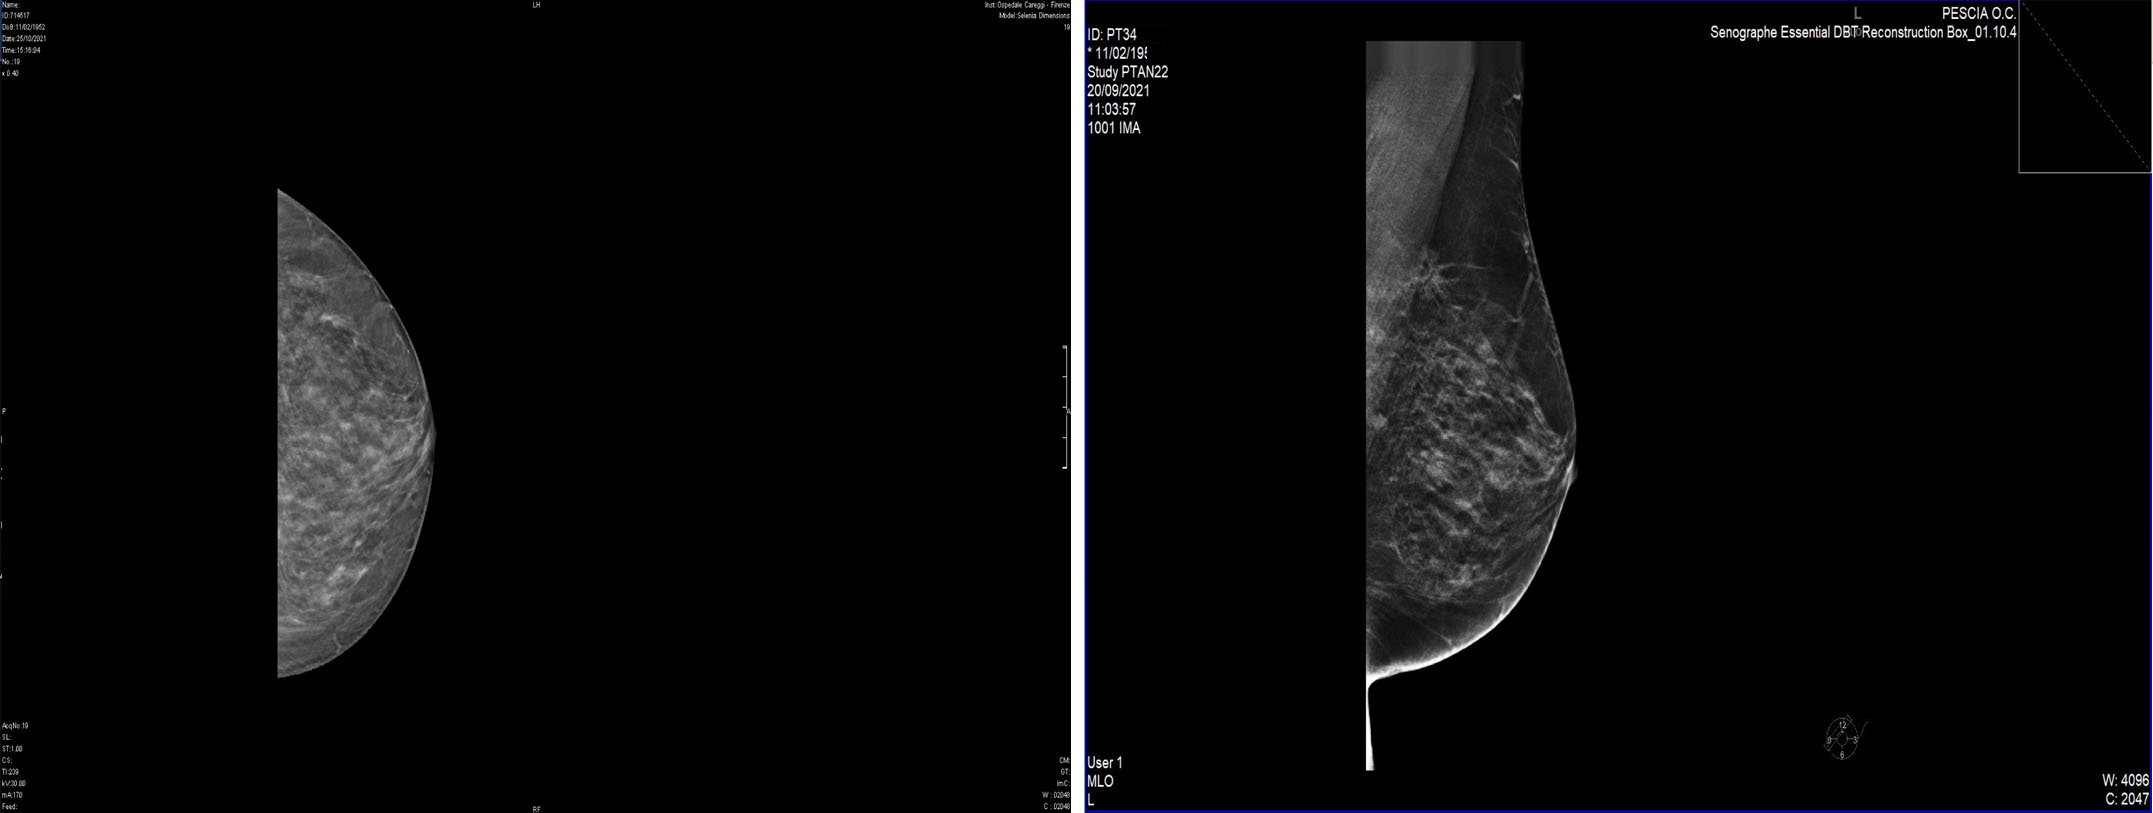

CASE 8. INFILTRATING LOBULAR BREAST CANCER

Mammography confirms the presence of a small area of ​​parenchymal distortion on the deep planes of the left QSI, with a polylobed shape, not present in the previous control, without R3-type microcalcifications.

For further confirmation, the patient is invited to perform a breast MRI, which, however, due to the presence of metal wires from previous maxillofacial surgery, must be replaced with a CESM (contrasted enhanced spectral mammography) mammography at the Careggi Hospital; the examination identifies two areas of impregnation type irregular adjacent mass and with a maximum size of 16 and 12mm with a total extension of 31mm, referable to the index lesion; it is not possible to evaluate the relationship with the pectoral muscle behind it because the lesions are only partially included in the field of view of the method.